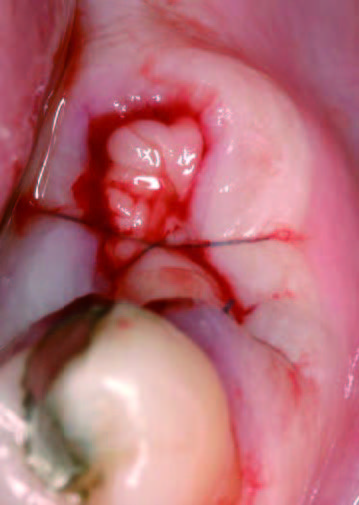

PRGFあり

抜歯とEndore填入

抜歯後にできた穴にPRGFを注入すると、上皮や骨の再生が促進され、短期間で穴が塞がります。また、抜歯後の痛みや腫れも軽減されるため、回復がスムーズに進みます。